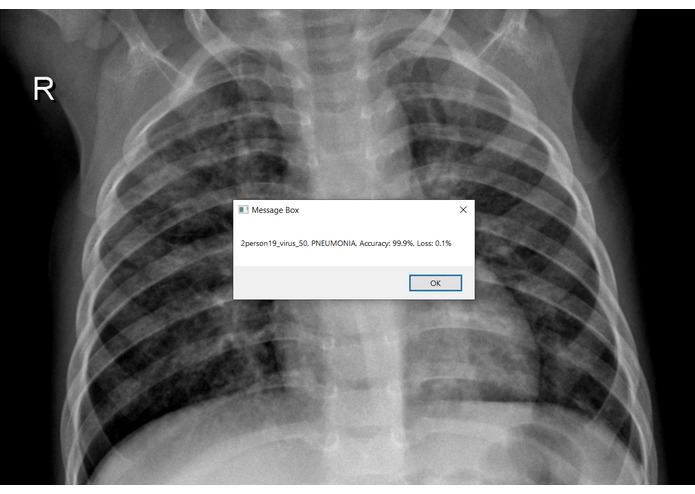

UIPath: After saving the best deep learning model, I built a workflow in UIPath to automate my testing process. The workflow will load the deep learning model, ask the users to select their chest Xray image and use the pre-trained model to test on the selected image. The diagnosis results will be displayed in a message box along with the selected image. All results will be saved into a log so that users can keep track of their testing process.